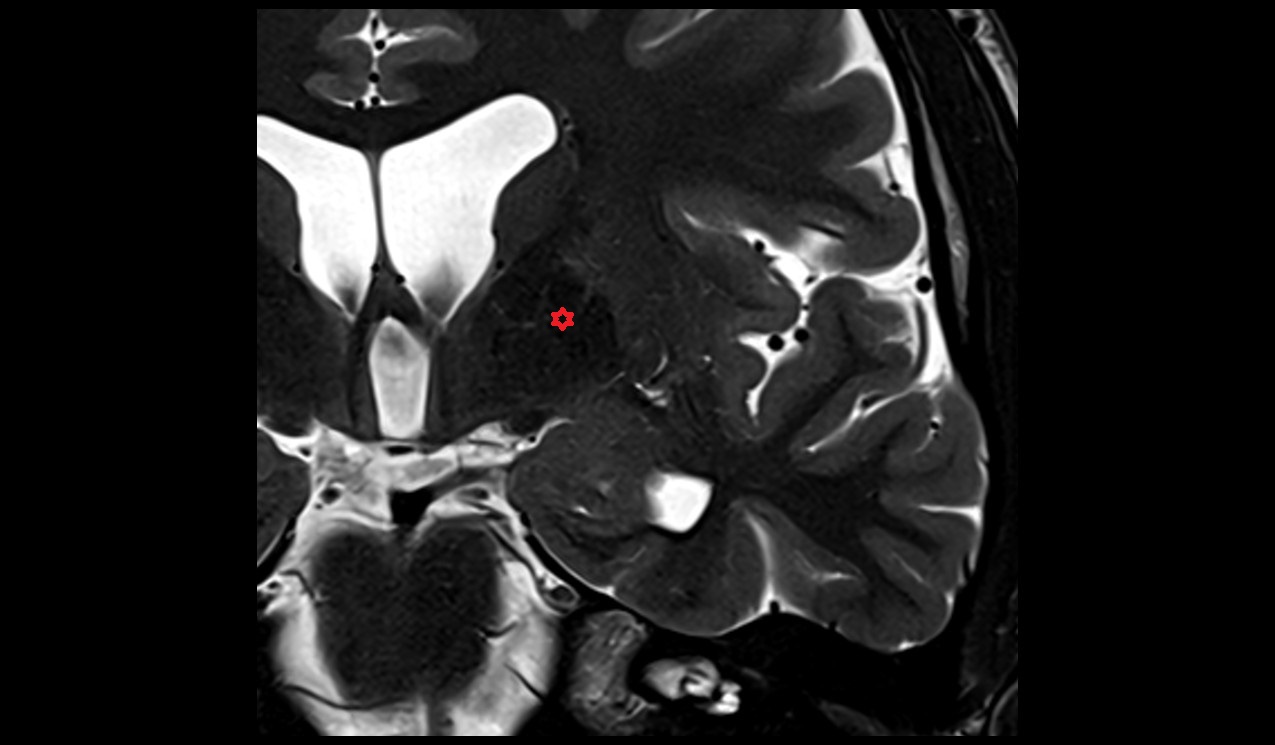

- Dentate nucleus

- Tonsil of cerebellum

- Cerebellar tonsil (H IX)